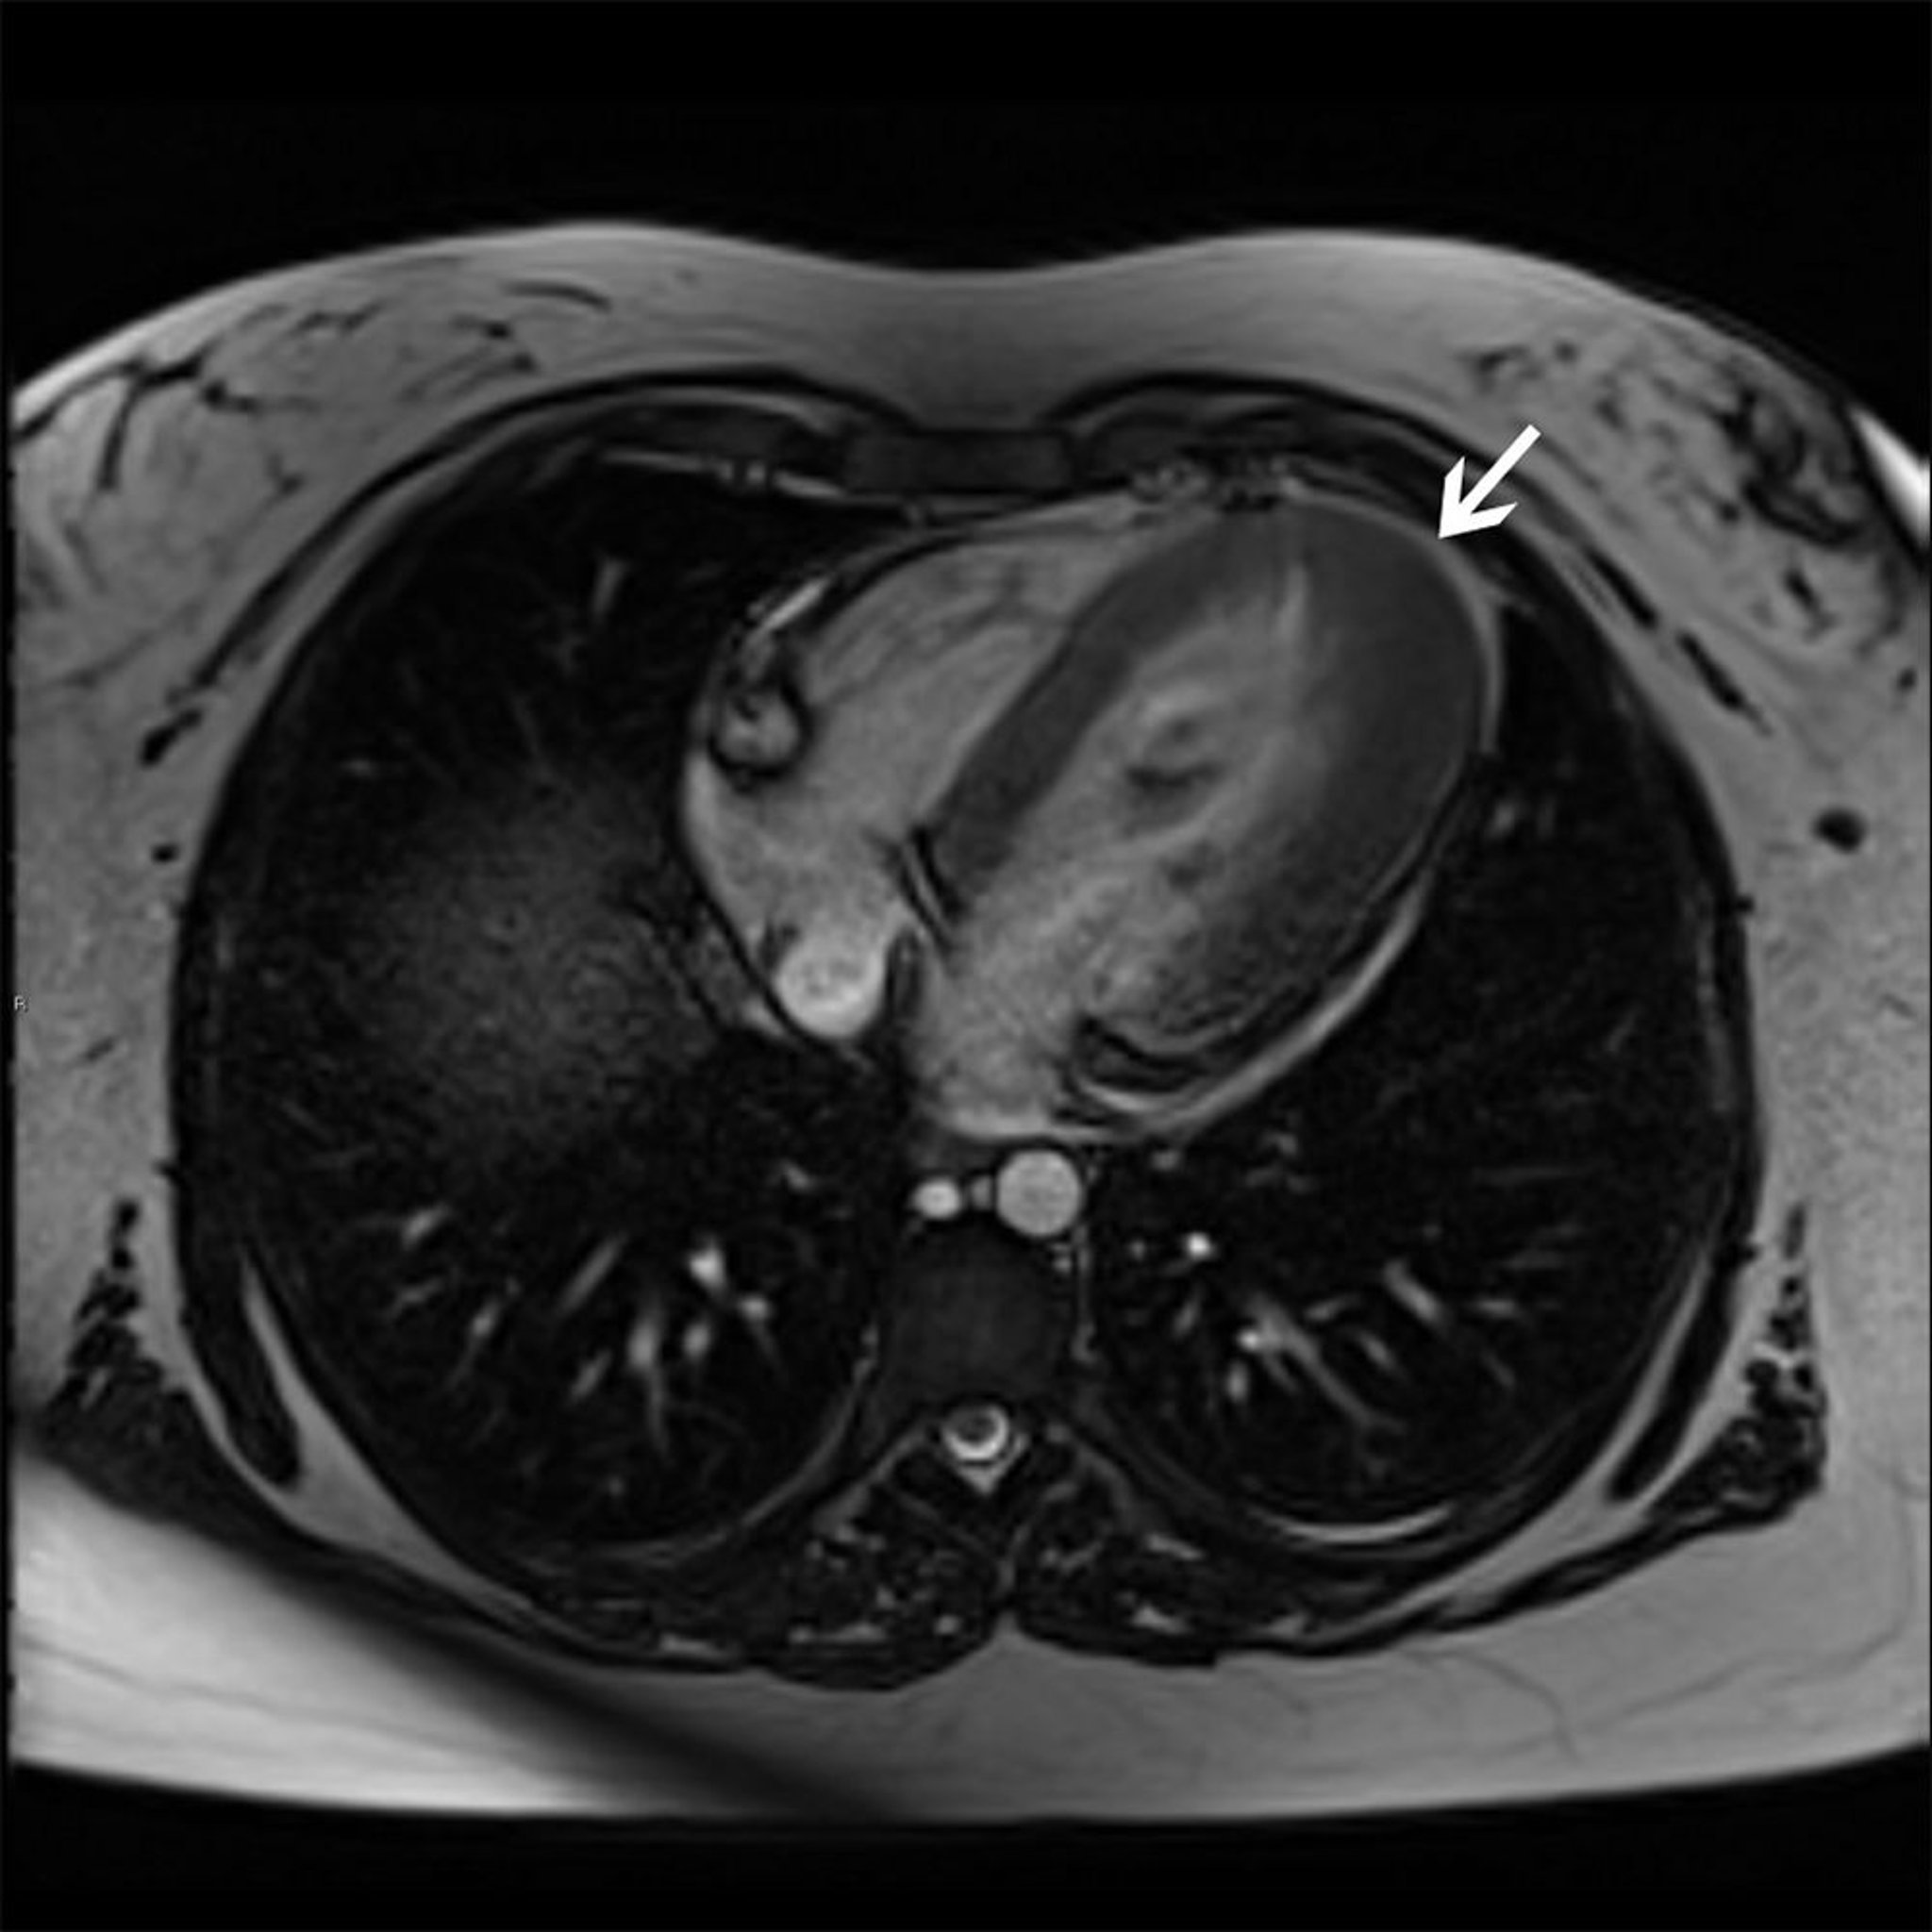

Hypertrophe Kardiomyopathie (apikale Variante)

Dieses kardiale MRT zeigt eine apikale Hypertrophievariante (Pfeil) der hypertrophen Kardiomyopathie.